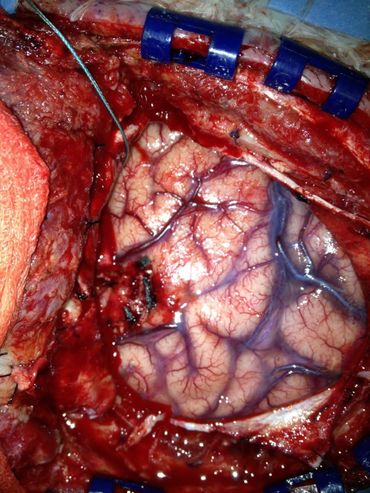

Understanding Brain Surgery: A 2013 Experience

Axial MRI scan showing detailed brain structures including eye sockets and brain tissue.